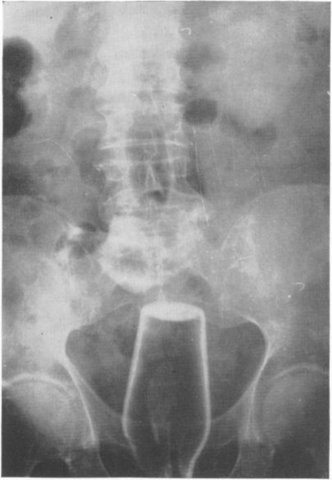

Poate ai văzut și tu la televizor cazul studentei care a rămas cu un vibrator în posterior sau cel al bărbatului care și-a băgat un ciocan în fund pentru a... sparge sâmburii de la cireșe. Deși ni se pare incredibil, există multe cazuri de acest gen, în care anumite persoane s-au prezentat la Urgențe cu diferite obiecte blocate în partea dorsală.

Medicii se confruntă cu multe cazuri de acest gen. Printre cele mai ciudate lucrurile pe care medicii le-au găsit în fundul pacienților se numără diferite jucării, becuri, legume, sticle și deodorante. Ești curioasă ce au mai găsit doctorii în interiorul pacienților la radiografii? Vezi în galeria de mai sus!